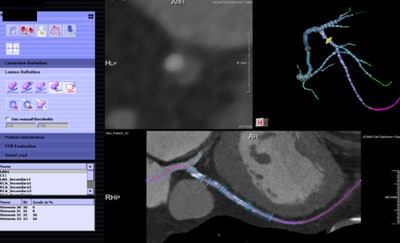

Patient with right coronary artery stenosis visualized on CCTA (a). Investigative FFR-CT application measures stenosis severity at 0.95 (c), confirmed at 0.94 on invasive angiography (d). All images courtesy of Dr. Koen Nieman.

Patient with right coronary artery stenosis visualized on CCTA (a). Investigative FFR-CT application measures stenosis severity at 0.95 (c), confirmed at 0.94 on invasive angiography (d). All images courtesy of Dr. Koen Nieman.The new algorithm processes the data in several steps, beginning with automatic data tracking, then segmentation of the vessels, and finally creating a 3D coronary artery model. The segmentation process takes about 16 minutes on a laptop computer, calculation another 15 minutes per dataset, Nieman said. Similar to the original FFR-CT algorithm, the user must know the left-ventriuclar mass to calculate the blood flow, he said.

Noncommercial work-in-progress FFR-CT application from Siemens Healthcare estimates blood flow in vessels.

Noncommercial work-in-progress FFR-CT application from Siemens Healthcare estimates blood flow in vessels.In a study originally presented at the 2014 European Congress of Radiology, Nieman and his colleagues at Erasmus examined 106 patients undergoing both coronary CTA and catheter-based FFR. Patients with prior stenting, calcium scores greater than 2000 or poor image quality were excluded.